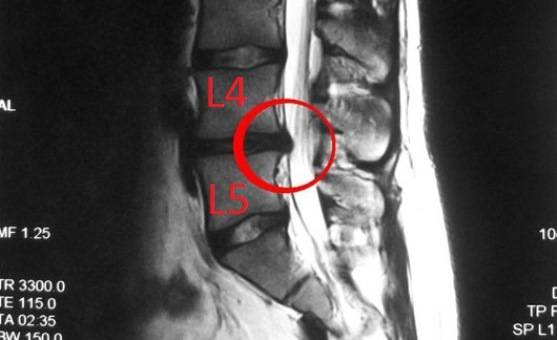

Локализации грыжи в l4-l5

Когда дорзальная диффузная грыжа межпозвонковых дисков локализуется в l4-l5 отделах, для больного она сопровождается следующими симптомами:

- очень сильные боли по всей спине, которые усиливаются при любых движениях и напряжениях, в том числе чихании и кашле;

- боль и онемение стоп и пальцев нижних конечностей, отечность.

Грыжа l4-l5 позвонков составляет 46% от общего числа всех грыж и является наиболее опасной, так как может привести к нарушению работы органов малого таза, ограничению движений. Участок позвоночника, состоящий из l4-l5 позвонков, является последним сегментом, поэтому испытывает наибольшую нагрузку и наиболее уязвим.

Если защемление позвонков l4-l5 будет продолжать прогрессировать, а больной попытается оттянуть поход к врачу, может произойти защемление отдельных участков спинного мозга и паралич.